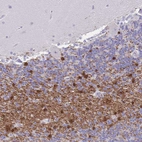

Immunohistochemistry analysis in human cerebral cortex and liver tissues using HPA038296 antibody. Corresponding ERMN RNA-seq data are presented for the same tissues.